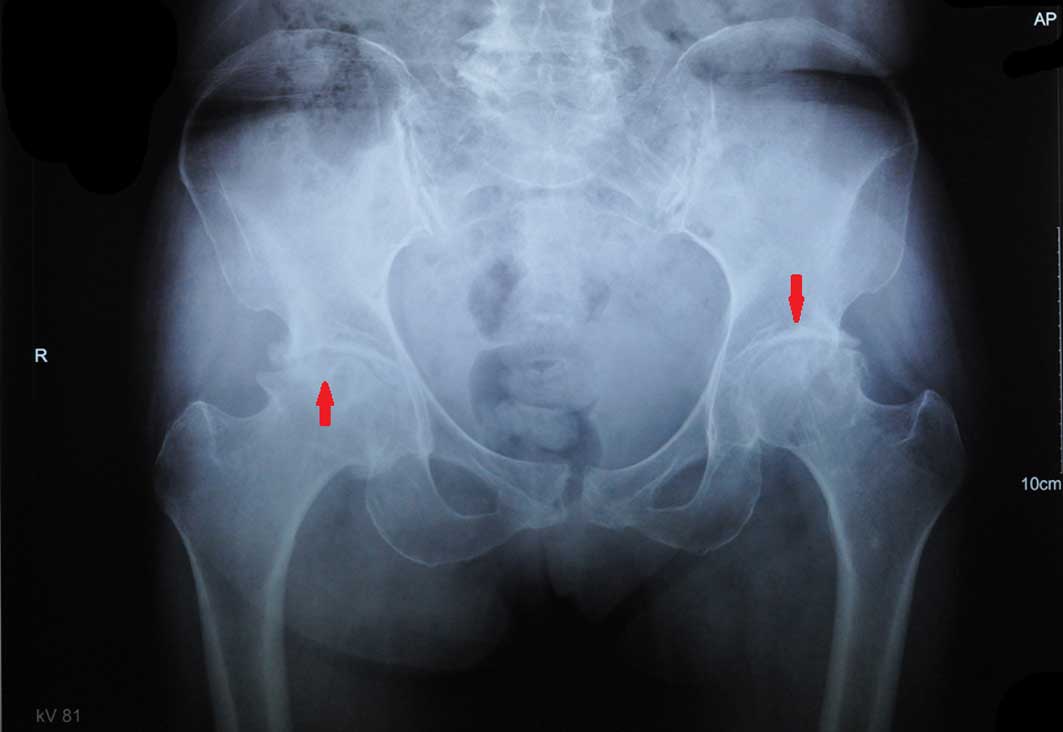

Osteoarthritis is a commonly occurring disease, with

the clinical manifestations of joint pain, swelling and progressive

loss of function (Fig. 1).